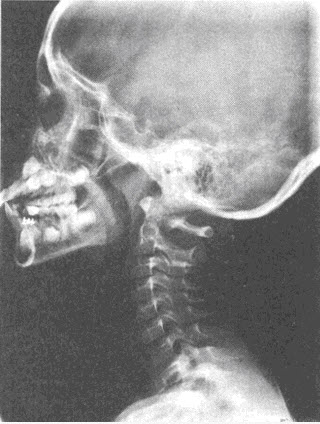

患儿,男,5岁,反复呛咳,张口呼吸,有鼾声,鼻腔分泌物多。X线检查如图所见,最可能的诊断是()

A、鼻窦炎

B、鼻息肉

C、扁桃体炎

D、腺样体肥大

E、鼻炎

D